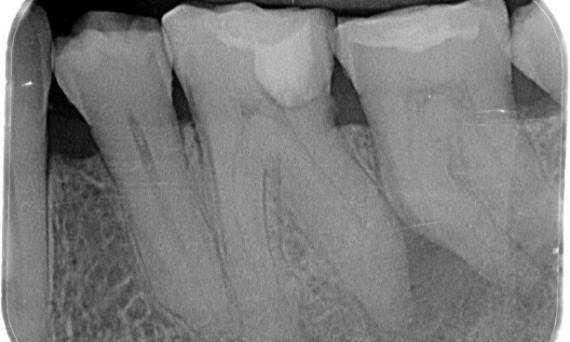

Avant : L’examen a révélé une lésion carieuse liée à la première molaire mandibulaire droite. L’examen radiographique a révélé la proximité de la lésion avec la corne pulpaire et, en l’associant à la plainte principale, un diagnostic final de pulpite chronique irréversible a été posé.